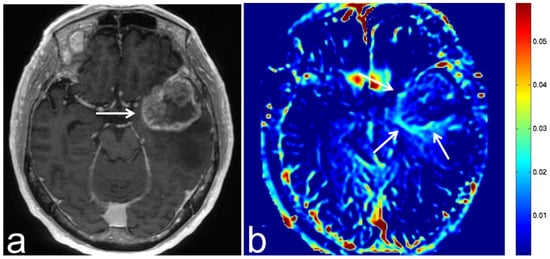

5.3. Glioblastoma

5.4. Malignant Lymphoma

5.5. Brain Metastasis